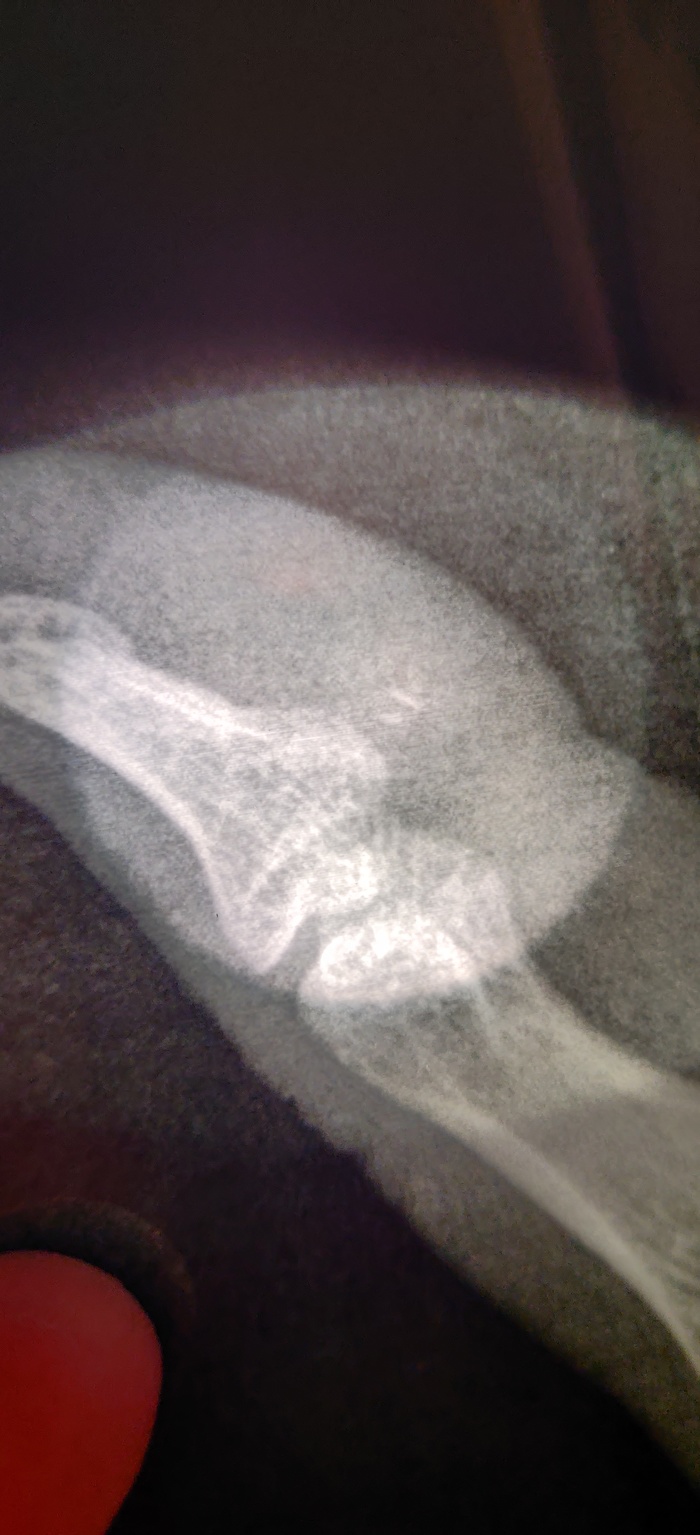

На рентгеновском снимке осколок стекла в пальце.

Было принято решение делать повторный рентген.

На нем обнаружились осколки меньшего размера.